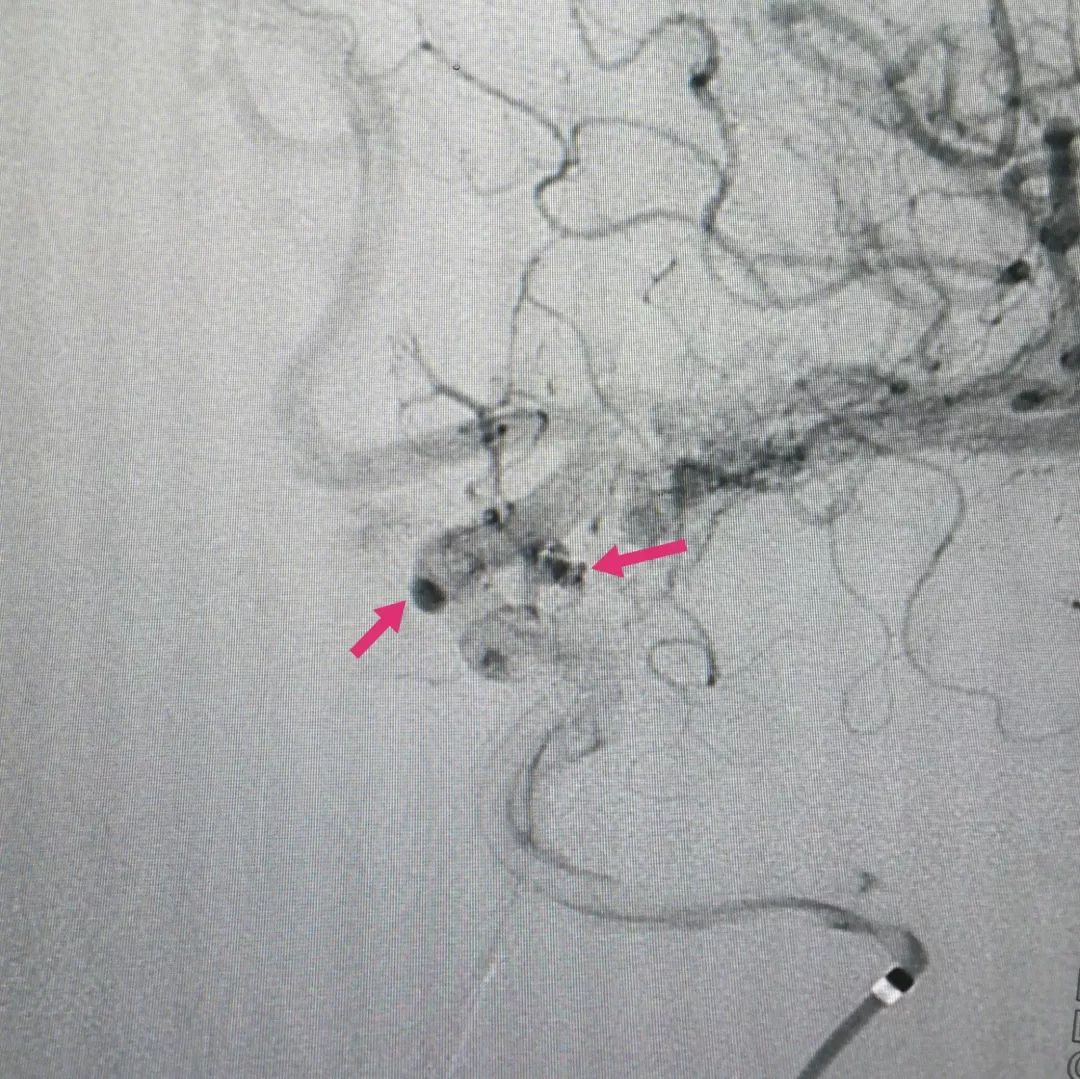

手术后复查脑血管造影可见动脉瘤已经大部分再显影,残余瘤腔内造影剂明显滞留(下图),提示动脉瘤内血流缓慢,而这就是密网支架的独特效果。根据冬雷脑科医生集团的临床经验,微小动脉瘤一般半年后的完全治愈率是100%